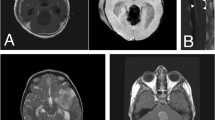

The primary tumors and their recurrences (Table 1) were analyzed histologically using microscopy of H&E and Ki67 staining. As opposed to primary specimens (Fig. 2a, e), H&E-stained recurrences revealed a loss of architecture with features of primary AT/RT, such as mesenchymal, epithelial, or rhabdoid architectures [34] being less prominent (Fig. 2c, g). The number of mitotic figures was significantly increased in recurrences (p = 0.04, Fig. 2a, c, e, g, i). Ki67 staining resulted in a significantly intensified labeling in recurrences, with an average of approximately 48% Ki67-positive nuclei, compared to 34% in primary tumors (p = 0.017, Fig. 2b, d, f, h, j). This suggests that recurrent tumors undergo changes that may be related to additional molecular alterations and even more aggressive tumor growth.

Histological features of recurrent AT/RT compared to primary tumors. Recurrent tumors demonstrate loss of architecture, increased number of mitotic figures using H&E staining (a, c, e, g), and intensified Ki67 labeling (b, d, f, h). All samples showed negative SMARCB1 staining (a, e: square box below right), confirming the diagnosis of AT/RT. i Mitotic activity increased in recurrent tumors. j Ki67 index was heightened in recurrent AT/RT compared to primary tumors. HPF high-power-field